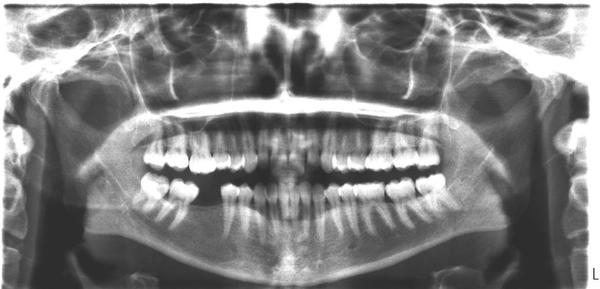

Holky pokud se nekdo vyzna muzete mi zkouknout ten rengen??

Byla jsem na zubni hygieně a pak u zubare na kontrole, a rikala jsem mu, ze mam na strane jak mi chybi sestka pod sedmickou mozna uz skoro pod osmickou na dasni takovej hrbolek….jazykem to necejtim jen kdyz prejedu prstem…jak kdyby uzlinka podobny tomu to je, takova mekka cast dasne pohybliva mozna do 5mm…ale je to zenvnitr ne zvenku dasne…je to melky hybe se to…doktor mi na to nic nerekl na druhy strane mi odvrtal kaz, a prej kontrola dalsi za pul rok…